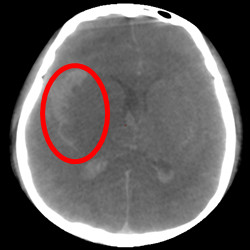

▲介入手术后高清类CT评估,早期发现出血并发症,

尽早制定治疗策略,提高手术安全和效率。